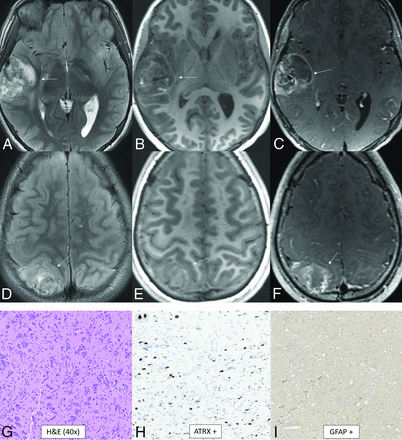

Diffuse pediatric-type high-grade glioma, H3 wild-type and IDH wild-type. MR images demonstrate diffusely infiltrating masses in the bilateral temporal lobes with mild mass effect, T2-FLAIR (A) and T2-hyperintensity (B, anterior arrows), and no enhancement (C). There is additional T2-FLAIR and T2-hyperintensity in the dorsal pons and posterior fossa leptomeningeal enhancement (posterior arrows). Histology reveals a high-grade diffusely infiltrating astrocytoma with high mitotic activity (D). The tumor shows ATRX retention (E) and wild-type IDH status (F) on immunohistochemical stains. Whole-genome methylation analysis showed a match to diffuse pediatric-type high-grade glioma. The tumor was H3 wild-type and IDH wild-type and had a TERT promoter mutation, which was identified on the neuro-oncology targeted next-generation sequencing panel.

Infant-Type Hemispheric Glioma